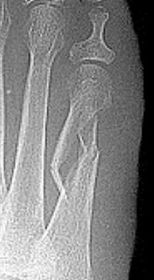

Describe what has happened at the shaft of the 3rd met | Exuberant periosteal new bone production. May have resulted if a stress fracture was not treated and the patient continued weight bearing activities. |